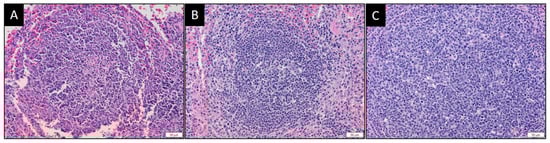

3.5. MYXV and MYXVorfC Induce Similar Histologic Lesions

3.6. MYXVorfC Stimulated Follicular Hyperplasia in Lymphoid Tissues